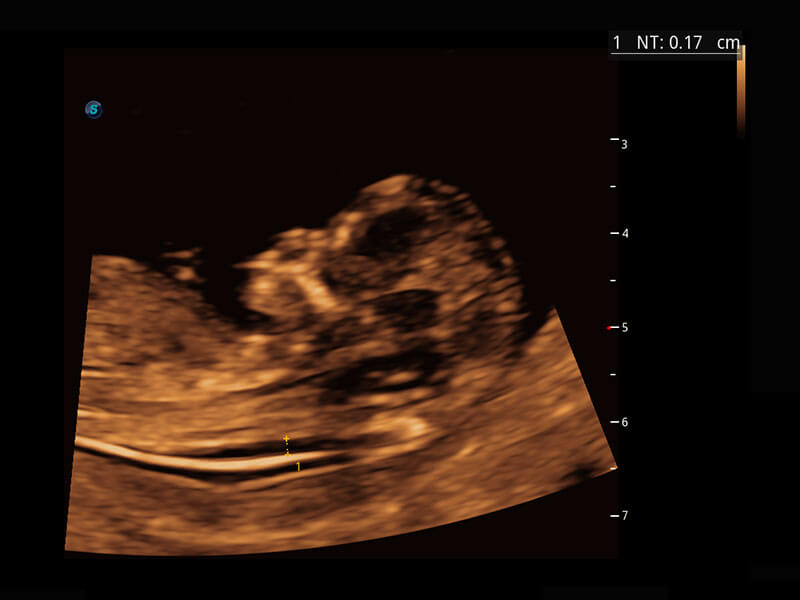

P60在胎儿早孕期超声筛查中为您带来优异的图像质量。

• 早孕-胎心